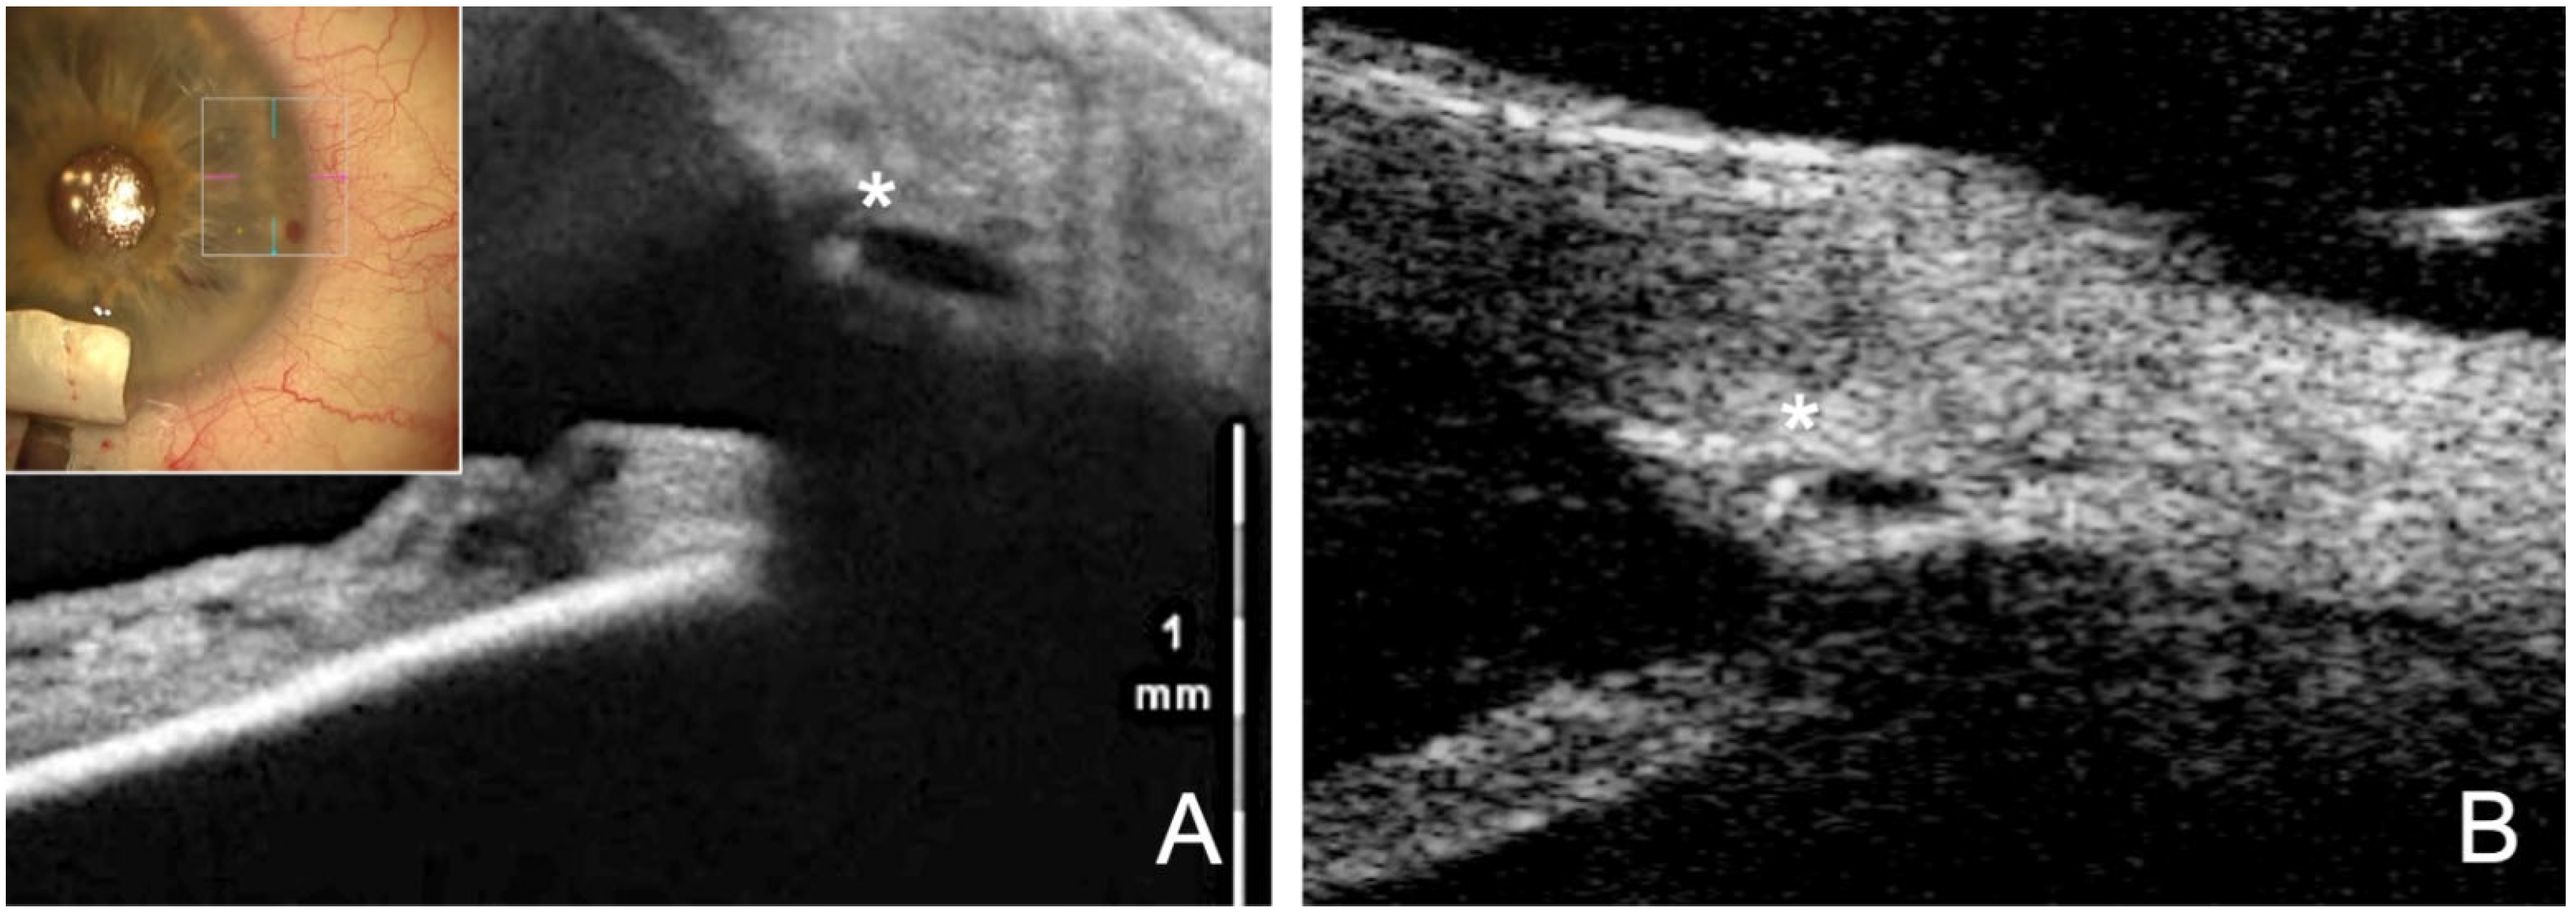

- Szurman, P.; Mansouri, K.; Dick, H.B.; Mermoud, A.; Hoffmann, E.M.; Mackert, M.; Weinreb, R.N.; Rao, H.L.; Seuthe, A.M. Safety and performance of a suprachoroidal sensor for telemetric measurement of intraocular pressure in the EYEMATE-SC trial. Br. J. Ophthalmol. 2023, 107, 518–524. [Google Scholar] [CrossRef]

- Mariacher, S.; Ebner, M.; Januschowski, K.; Hurst, J.; Schnichels, S.; Szurman, P. Investigation of a novel implantable suprachoroidal pressure transducer for telemetric intraocular pressure monitoring. Exp. Eye Res. 2016, 151, 54–60. [Google Scholar] [CrossRef] [PubMed]

- Szurman, P.; Gillmann, K.; Seuthe, A.M.; Dick, H.B.; Hoffmann, E.M.; Mermoud, A.; Mackert, M.J.; Weinreb, R.N.; Rao, H.L.; Mansouri, K. EYEMATE-SC Trial: Twelve-Month Safety, Performance, and Accuracy of a Suprachoroidal Sensor for Telemetric Measurement of Intraocular Pressure. Ophthalmology 2023, 130, 304–312. [Google Scholar] [CrossRef]